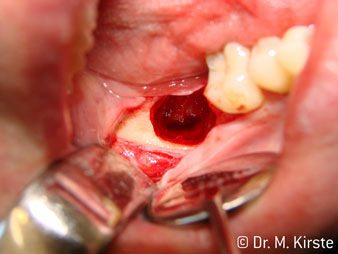

45° açılı angldruva geniş avantaj yelpazesi sebebiyle özellikle seçildi. Bu enstrümanın geliştirilme nedeni olan cerrah meslektaşlarım angldruvaların kısıtlı alanlardaki çalışma yeteneğini yakında takdir edeceklerdir. Özellikle gömük diş çekimlerinde (res. 2) yumuşak dokunun yanak bölgesine doğru yarılmasına gerek kalmaz(res. 3). Angldruvanın kafa dizaynı sayesinde retromolar bölgede hızlı ve güvenli çalışma sağlar.

45° açılı angldruva çok rahat kavranıyor. Angldruva çalışırken işaret parmağınızın açısını takit ettiğini görebilirsiniz, planladığınız işlemi kusursuz bir şekilde tamamlarsınız. (res. 1)”